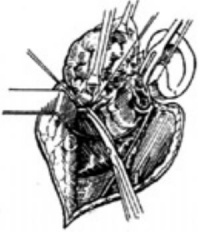

4、切除腮腺浅叶及肿瘤,将已分离出的腮腺上、下极及前缘连同腮腺导管一起向后方掀起,继续沿神经分支表面向总干分离,最后切继腮腺峡部,此时腮腺浅叶连同位于其内的肿瘤被一并摘除。如肿瘤位于腮腺深叶,亦需摘除浅叶后方能在明视下摘除深叶的肿瘤。

2、防止血管损伤 巨大的腮腺混合瘤,尤其是来源于腮腺深叶的肿瘤与颈部大血管关系密切,因此分离时尽可能采用钝性分离,避免强力牵拉。

3、暂离断下颌骨 对颌后腮腺深叶肿瘤切除有困难时,为了扩大手术野,可将下颌骨向前方脱位,如肿瘤伸入咽侧,肿瘤过于巨大时,可将下颌骨锯断,拉开两断端。以使术野开阔,切除肿瘤后用骨间固定法使下颌骨复位。